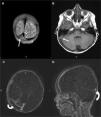

Patient 2A 2.5-year-old boy with no significant past medical history presented to our clinic with puffiness of the eyelids, edema of legs and decreased urine output. He had gained 2kg of weight in a week time. Physical examination revealed facial and pitting edema on extremities in addition to abdominal distension. Laboratory investigations showed Hb 14.9g/dl, htc 45.9%, platelet count 406,000/μL, total protein 3.7g/dl, albumin 1.4g/dl, serum cholesterol 382mg/dl and normal renal function tests. Urinary examination revealed heavy proteinuria; 244mg/m2/h. Serum C3 and C4 levels were normal. Nephrotic syndrome was diagnosed and the patient was put on 2mg/kg prednisone treatment. On the 4th day of treatment the patient complained of headache. Cranial CT was normal. On the 5th day he developed right 6th cranial nerve palsy. Magnetic resonance imaging and MRV showed thromboses in the superior sagittal, right transverse and sigmoid sinuses extending into the jugular system (Fig. 2). Intravenous hydration, low molecular weight heparin (LMWH) were started immediately. Screening for inherited thrombophilias was negative. On 10th day patient's headache subsided, focal neurological signs resolved. Remission was achieved on the 14th day of steroid treatment. The patient was discharged on steroid and LMWH. He had complete neurological recovery and has not experienced any complication during follow-up for 6 months.

Coronal T2-weighted (A) and transverse T1-weighted (B) MR images show hyperintense thrombus in transverse and sigmoid sinuses (arrows). Contrast-enhanced MR angiography axial (C) and sagittal (D) reformatted images demonstrate thrombus as hypointense filling defects in right transverse sinus (curved-arrows).